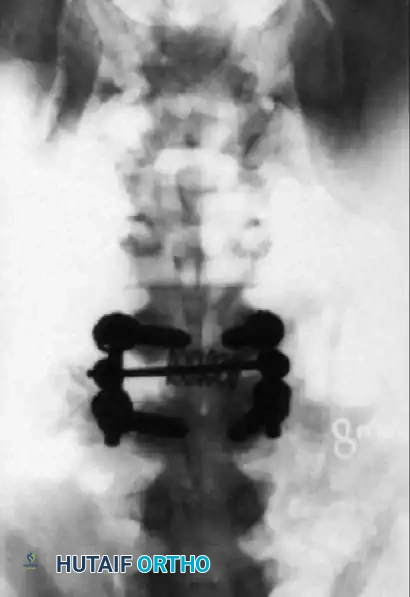

Postoperative lateral radiograph showing successful reduction of the anterolisthesis, restoration of disc height with an interbody cage, and solid posterior pedicle screw fixation.

Postoperative AP radiograph demonstrating the posterior construct, including pedicle screws and a cross-link (if utilized), ensuring rigid stabilization of the scoliotic and translated segments.